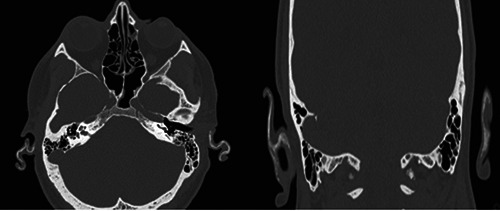

石化耳是一种罕见的临床实体,其特征是正常的柔性耳廓软骨进行性硬化,导致部分或完全耳廓僵硬。在许多情况下,它提供了有价值的临床线索,使临床医生能够在未得到诊断的患者中发现内分泌病变(特别是Addison病)。我们提出了第一个记录的石化耳病例,导致继发性肾上腺素减退和生长激素缺乏症(GHD)的诊断。此外,我们回顾了相关文献。石化耳综合征可能是其他全身性疾病的一种被低估的临床表现。有时,即使在没有典型特征的情况下,它也可以作为怀疑潜在内分泌疾病的有用而简单的临床线索。

Petrified ear is a rare clinical entity characterized by the progressive hardening of normal, flexible auricular cartilage, leading to partial or complete auricular stiffness. In many cases, it provides a valuable clinical clue that allows the clinician to detect endocrinopathies (particularly Addison's disease) in a patient who has not received a diagnosis. We present the first documented case of petrified ears, which resulted in the diagnosis of both secondary hypoadrenalism and growth hormone deficiency (GHD). Additionally, we review the relevant literature. Petrified ear syndrome is probably an underreported clinical manifestation of other systemic disorders. It may, at times, serve as a valuable and simple clinical clue to suspect underlying endocrinopathies even in the absence of typical features.